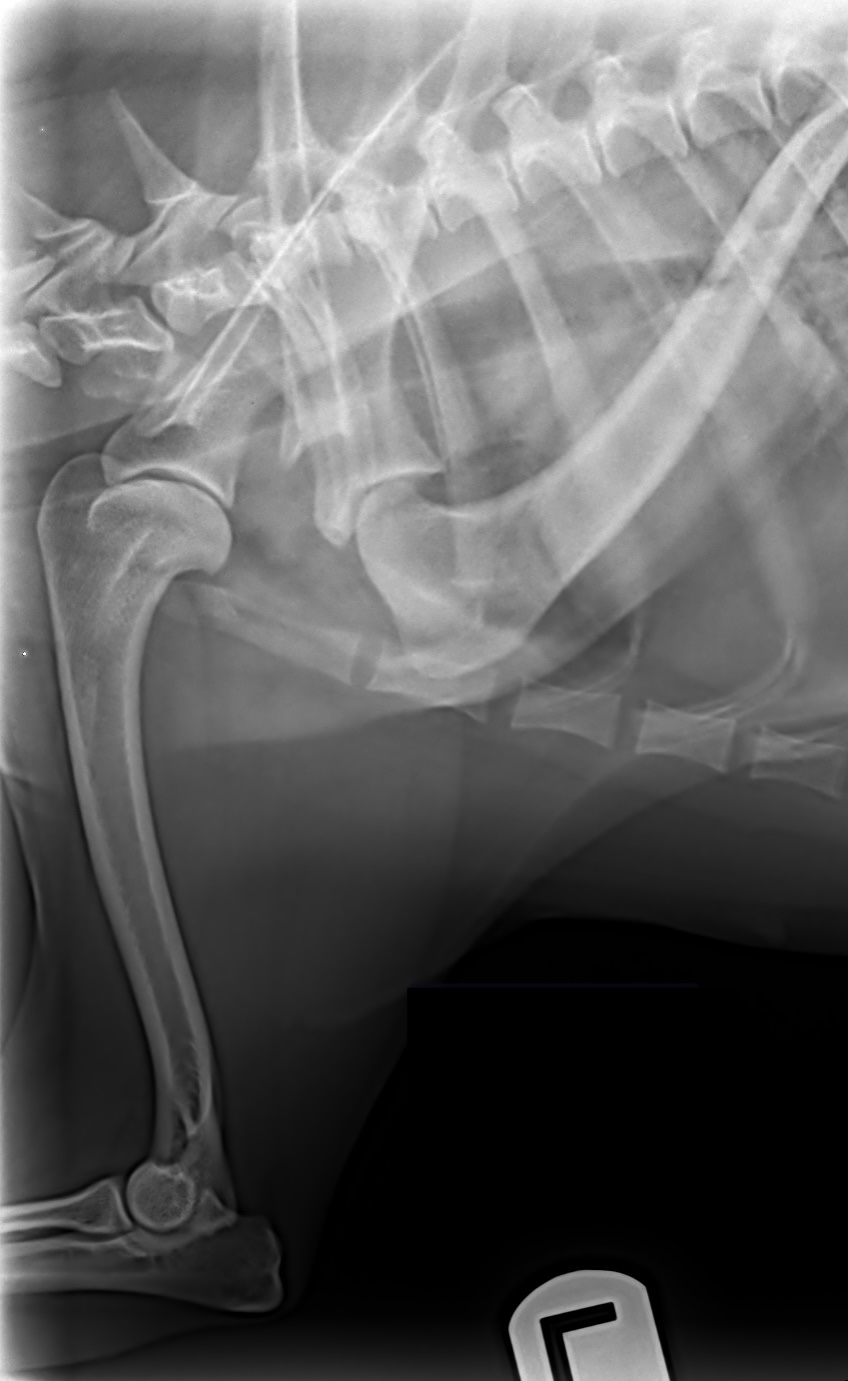

ofa | shoulder

rating | no osteochondrosis or djd